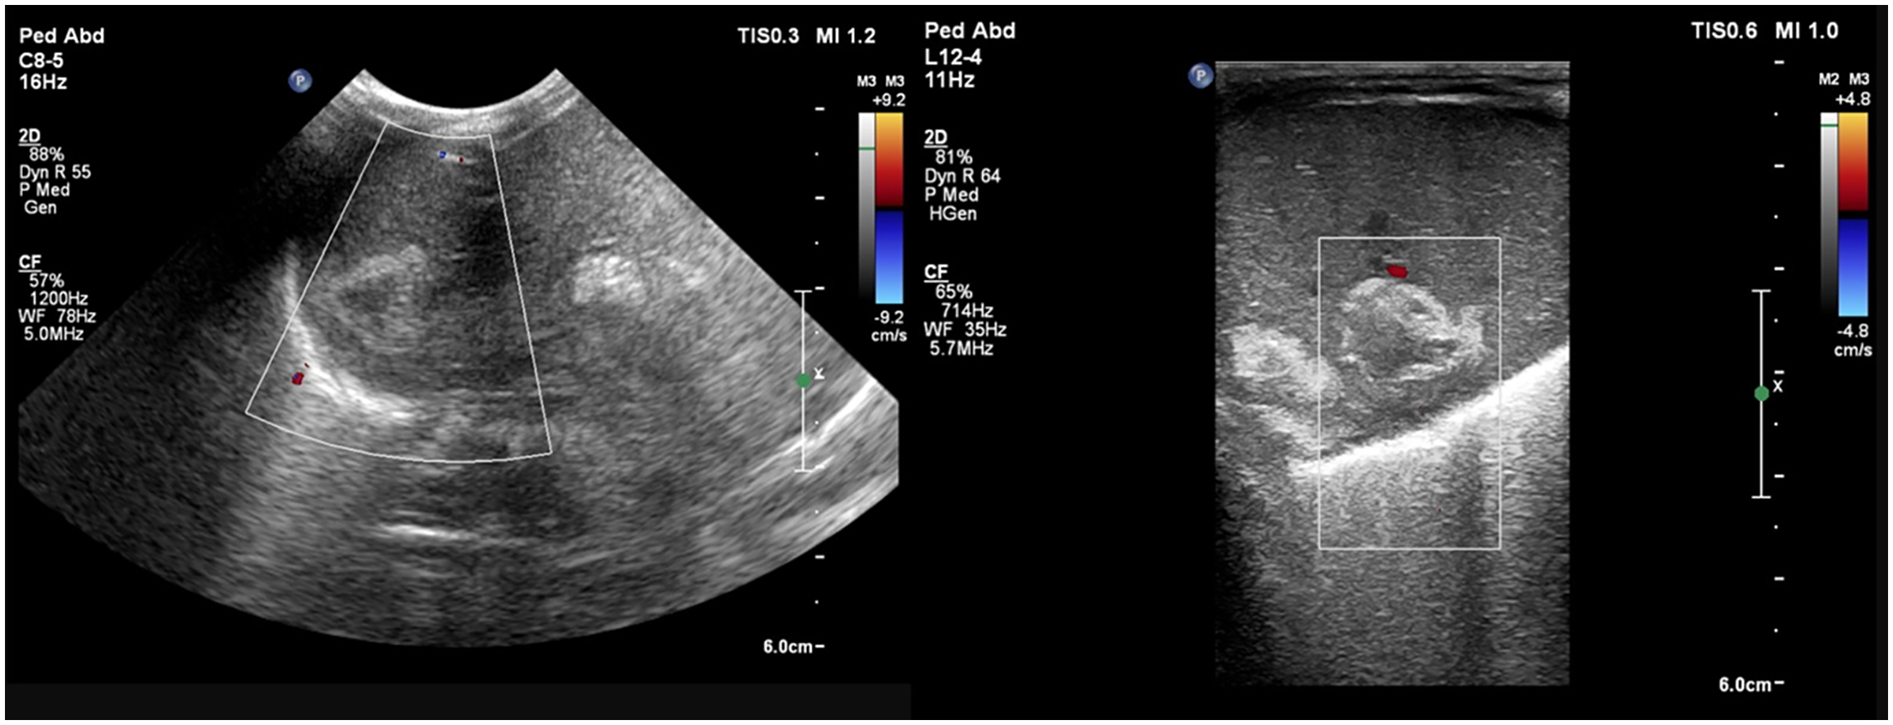

A preterm infant (GA 27 + 4 weeks), weighing 970 g, was born via emergency caesarean section for a premature preterm rupture of membranes since a week. The mother received intrapartum antibiotics and a single dose of steroid prior to delivery. In the NICU, the infant required intubation for significant respiratory distress and two doses of surfactant subsequently. First-line antibiotics were started; the umbilical venous catheter (UVC) and umbilical arterial catheter (UAC) were secured. The initial hemogram and CRP were normal. Minimal enteral nutrition was started on day 2. The patient was extubated to NIV support on DOL 6. On the same day, a clinical pallor was observed, and the complete blood count revealed a drop in hemoglobin levels to 119 gm/L (from 134 gm/L a day prior). There was no hypotension or metabolic acidosis on blood gas. Packed cell transfusion was arranged, and a bedside POCUS screening was performed for concealed hemorrhage. The cranial ultrasound result was normal, while the abdominal ultrasound revealed multiple well-defined heterogeneous hypoechoic lesions with internal septations in the right lobe of the liver, the largest one measuring approximately 3 × 2 cm with a hyperechoic wall. There was no internal or perilesional vascularity on Doppler (Figure 3). The possibilities of liver abscess or liver hematoma were considered; umbilical catheters were removed and antibiotics escalated. However, serial CRPs were negative on DOL 6, 7, and 8, respectively, and blood cultures were sterile. The baby remained clinically stable, achieved full feeds, and antibiotics were stopped on day 10. An abdomen magnetic resonance imaging (MRI) performed on DOL 13 was suggestive of a well-defined cystic lesion in the right lobe of the liver with peripheral hemosiderin deposit, suggestive of subacute or chronic hematoma. Further hospital stay was uneventful, and the baby was discharged home on DOL 54 in a stable condition. Follow-up abdominal ultrasounds (day 18 and day 66) showed a progressive decrease in the size of the lesion.

Figure 3

Liver POCUS shows well-defined heterogeneous hypoechoic lesions with a hyperechoic wall and subtle internal septations in the right lobe of the liver. Doppler evaluation shows no internal or perilesional vascularity.

In view of the patient’s clinical deterioration and unexplained hepatomegaly, a screening point-of-care abdominal ultrasound was performed, which showed a thick, hyperechoic walled lesion measuring 5 × 2.8 × 3.7 cm, with a cystic center, with mobile echoes within, and no increase in vascularity, suggestive of an abscess in the right lobe (Figure 4). Other abdominal organs, like spleen and kidneys, did not show any focal lesion. The results of the cranial ultrasound were normal. The findings were confirmed by a radiologist.

Figure 4

Liver POCUS shows (A) a lesion with a thick and hyperechoic wall in the right lobe of the liver measuring 5 × 2.8 × 3.7 cm with (B) a cystic center and mobile echoes within the lesion, with no increase in vascularity suggestive of an abscess.